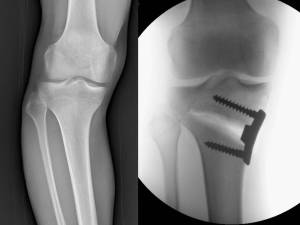

La componente di varismo, se presente, in questo caso si parla di varismo idiopatico (fig 5 AB), può essere ridotta con interventi di modulazione della crescita mediante applicazione di 8-plates sul versante esterno della cartilagine di accrescimento della tibia prossimale (fig 5 CD-EF).

Fig. 5: anni 11 e 8/12, tibia vara costituzionale con componente torsionale. DIC: 6 cm con rotule allo zenith (A), DIC: 5 cm con piedi extra ruotati di 30° (B); in pratica il varismo persiste anche con gli arti in extrarotazione. C) Quadro radiografico. D) La componente di varismo può essere migliorata con interventi di modulazione della crescita, mediante applicazione di piccole placche a forma di “8” in corrispondenza della parte laterale della cartilagine di accrescimento della tibia prossimale. E-F) In quest’immagine è possibile confrontare l’aspetto della ginocchia prima dell’operazione (E) e dopo 2 anni dall’intervento chirurgico di epifisiodesi asimmetrica tibiale esterna (F). L’asse meccanico delle ginocchia è migliorato, persiste invariata l’alterazione torsionale.

A fine accrescimento si possono eseguire interventi di osteotomia (fig 6 AB-CD).

Fig. 6: A-B) Anni 16, varismo idiopatico. Aspetto clinico e radiografico a fine crescita. C-D) Esempio di osteotomia correttiva mediante placca.